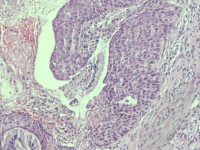

性别

女

年龄

38岁

临床诊断

宫颈病变

一般病史

宫颈癌筛查:HPV52(+)

标本名称

宫颈6点组织

大体所见

灰白色组织1块

可以诊断CIN几级

图1

HSIL(CIN3)累腺